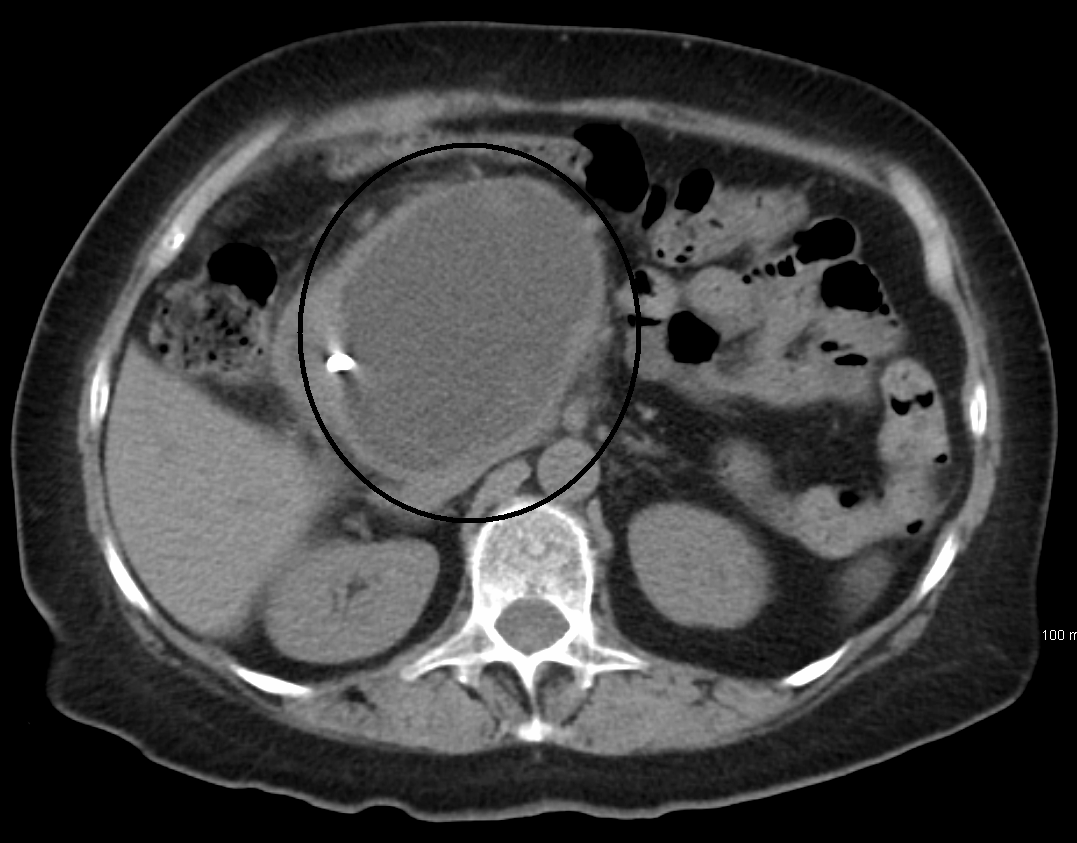

Pancreatic pseudocyst may develop as a complication of chronic pancreatitis. These are called pseudocyst since these are lined by fibrotic tissue in contrast to epithelium in true cysts. The pancreatic pseudocyst is mostly located in lesser sac. Pseudocysts are suspected when there is fever and persistently elevated pancreatic enzymes. The condition may be self-limiting. In other cases, surgical drainage may be required. Reference: https://surgery.ucsf.edu/conditions--procedures/pancreatic-pseudocysts.aspx Image via: https://surgery.ucsf.edu/conditions--procedures/pancreatic-pseudocysts.aspx